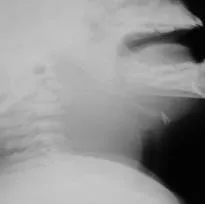

- Examination: bulge in the posterior pharyngeal wall.

- Lateral x-ray shows: Retropharyngeal abscess.

Management

- Best management:

- Transoral incision and drainage.

- IV antibiotics.